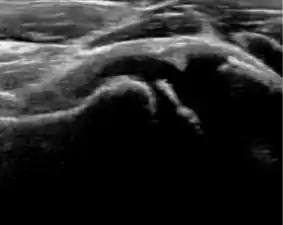

Ultrasound

Ultrasound is the first-choice technique for diagnosis of newborns hip dysplasia. In experienced hands with appropriate technology, ultrasound can also be useful during the first year of life. Some European healthcare systems encourage universal ultrasound screening in neonates between the sixth and eighth weeks. Although it shows higher initial costs caused, it leads to significant reduction in the total number and overall costs of dysplastic hips undergoing operative and nonoperative treatment.[1]

Ultrasound allows categorizing pediatric hips, according to Graf’s criteria, in four main types: normal, immature, and dysplastic (subluxed and dislocated). This classification is based on measurements of the acetabular inclination angle (alpha), cartilage roof angle (beta), and infant age. The femoral head coverage can also be determined by dividing the length of the femoral head covered by the acetabular fossa and the diameter of the femoral head. Its lower normal limits are 47% for boys and 44% for girls (Figure 11).[1]

During childhood, ultrasound is a quick method to assess hip pain and quite often may be used to avoid use of irradiating techniques, such as radiography or CT. Ultrasound allows evaluation of joint effusion, synovial thickening and neovascularity, the bone/cartilage contour, and the femoral head-neck alignment. Although sonography is extremely sensitive in detecting increased synovial fluid, it is nonspecific and cannot be used with accuracy to determine the type of fluid. Transient synovitis of the hip, despite being the most frequent cause of pain in children between 3 and 10 years, remains a diagnosis of exclusion. It usually shows anechoic fluid, but echogenic fluid can also be found. The effusion is considered pathologic when it is measured at >2 mm in thickness. The differential diagnosis is wide, including osteomyelitis, septic arthritis, primary or metastatic lesions, LCPD, and SCFE. Discrimination from septic arthritis is challenging, often requiring joint aspiration. In septic arthritis, US is able to demonstrate a hip joint effusion, synovial thickening, and cartilage damage, although the appearances are nonspecific.[1]

A step between the head and the physis can be detected in children with SCFE, while abnormalities in the femoral head contour may suggest the presence of LCPD. In both cases, radiographs are mandatory to confirm diagnosis and severity (Figure 12).[1]

Figure 12:

-

Normal ultrasound appearance of the femoral head-neck junction. -

Joint effusion in transient synovitis of the hip. -

Flattening of the femoral head in a patient with Perthes disease. -

Step in the femoral head-neck junction in a patient with SCFE.